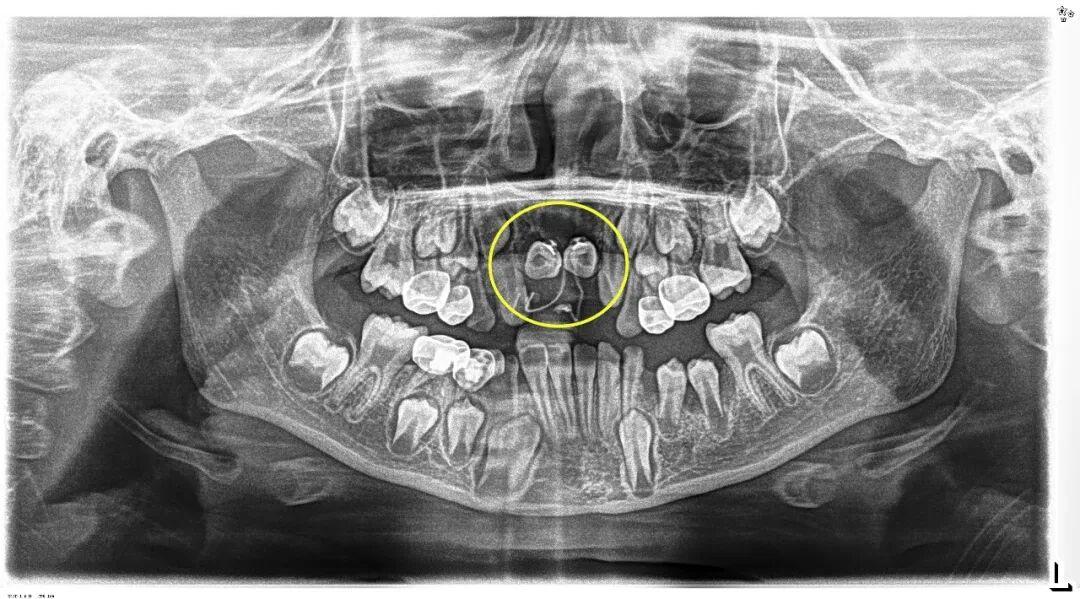

埋伏牙一旦发现,应及早处理。针对小胡的情况,口腔团队在完成多生牙的拔除后,为埋伏牙粘接牵引装置,通过温和的正畸力对受影响的恒中切牙进行“牵引导萌”,“拉”回正常生长轨道。

术后小胡恢复非常顺利。第一次复查时,两颗恒中切牙的舌侧扣和弹性附件的影像,下图可见: